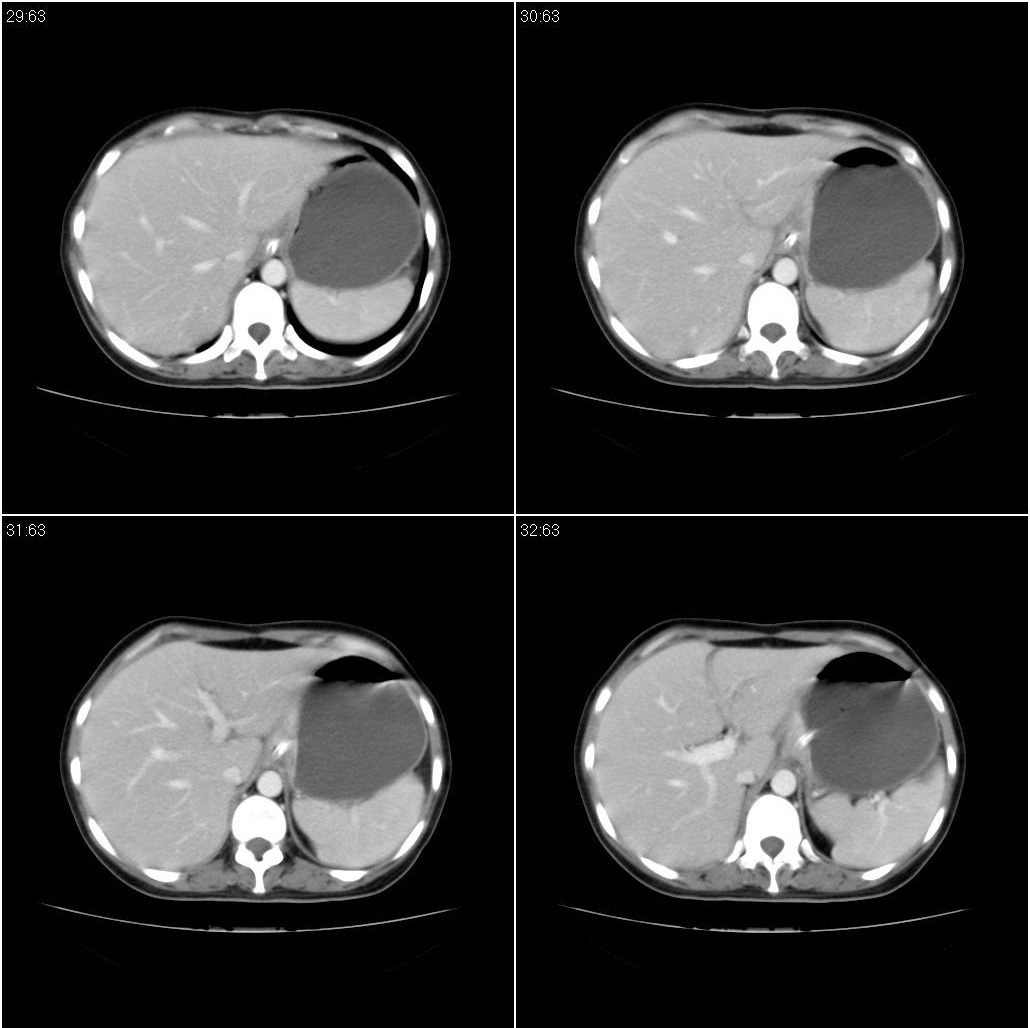

标题: CT21386:女性,33岁。4个月前因妊娠发现盆腔肿物。 [打印本页]

女性,33岁。4个月前因妊娠发现盆腔肿物。ca-125: 1100

胃癌,幽门梗阻

胃癌,幽门梗阻.

支持;胃癌【浸润】幽门梗阻.

胃窦贲门胃小弯好像都厚啊 ,胃窦处比较明显,而且胃腔扩张明显,考虑胃癌伴梗阻。

高密度影是胃肠减压的管子。